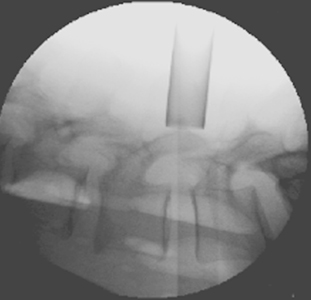

The surgery is performed through a small skin incision on the back.   A narrow tube is gently inserted through the soft tissue under fluoroscopy (x-rays) with the aid of a minimally invasive muscle retracting system. This retractor helps minimize damage to the muscles and soft tissue. With the aid of a high-powered microscope, the herniated disc can be removed with specially-designed microsurgical instruments to relieve pressure from the nerve root. The skin is closed using dissolvable sutures and sterile superglue. Some patient’s may require a back brace after surgery.

Minimally Invasive Microdiskectomy X-Ray